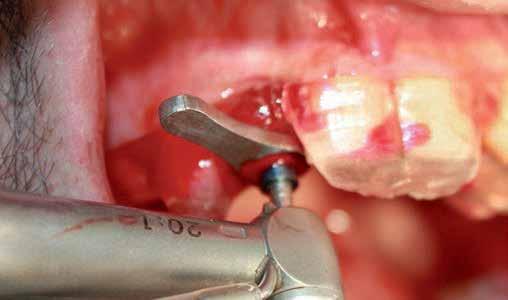

A systemic antibiotic (2g amoxicillin-clavulanic acid, per-orally) was administered to the patients 1 hour prior to the procedure. The patient’s mouth was rinsed with a solution of chlorhexidinedigluconate 0.2% for 2 minutes. After surgical guide printing, the tooth was extracted and the implant placed (IDI implant Implants Di usion International 23/25) following implant placement protocol using a fully guided CAD CAM surgical guide. 14 (fig 3,4,5)

Figure 5: Fully guided implant placement through the surgical guide using spoons. The implant was inserted at the planned position.